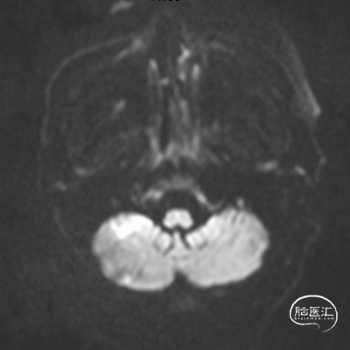

1.急查头颅MRI+RMA示:

2.右侧小脑半球、双侧枕叶、左侧颞叶脑梗塞;

3.桥脑区、双侧基底节区陈旧性脑梗塞;

4.脑白质脱髓鞘;

5.双侧椎-基底动脉、双侧大脑后动脉、右侧大脑前动脉闭塞;

6.右侧颈内动脉狭窄;

7.脑动脉硬化。

MRI

MRA